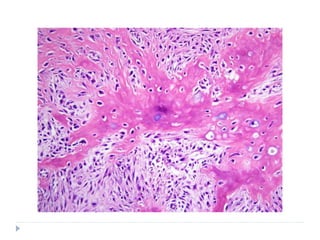

HISTOPATHOLOGY

 They vary in histologic grade

 WELL DIFFERENTIATED

 Multiple plump fibroblasts with pale eosinophilic cytoplasm and

deeply stained spindled nuclei

 Malignant cells are dispersed in rich collagen background

 Histologically normal mitotic figures are seen in few numbers

 Cells and nuclei are not pleomorphic

 INTERMEDIATE GRADE

 Cellular

 Have HERRING BONE PATTERN: parallel sheets of cell

arranged in intertwining whorls

 Slight degree of cellular pleomorphism

 Moderate amount of mature collagen